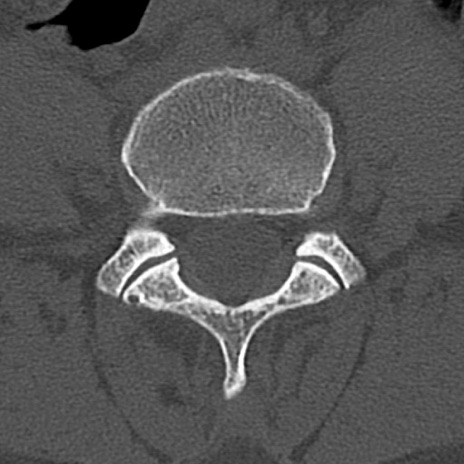

腰椎CT

横断像と矢状断像